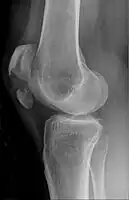

Types

The patella can break in various ways depending on the way it is injured, and into two or more pieces.[1] Types include transverse, the most common, with one fracture line;[5] marginal; osteochondral; and the rare vertical type, or stellate, where a direct compression force gives rise to a comminuted pattern.[5][7] Patella fractures can be further classified as displaced, where the broken ends of bone do not line up correctly and separate by more than 2mm, or undisplaced and stable where pieces of bone remain in contact with each other.[1][7] If fragments of patella bone stick out from the skin it is known as an open patella fracture, and closed if the overlying skin is intact.[1]